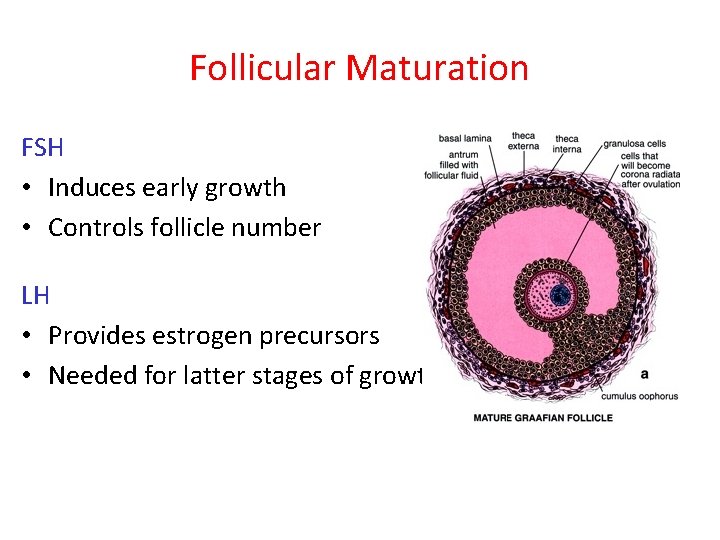

Follicular Maturation FSH • Induces early growth • Controls follicle number LH • Provides estrogen precursors • Needed for latter stages of growth